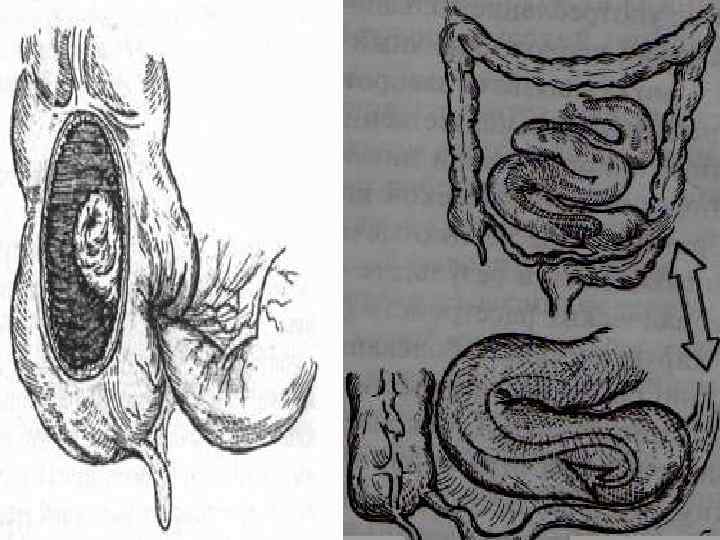

{ Схематическое изображение инвагинации тонкой кишки в слепую — двойная инвагинация { Схематическое изображение инвагинации тонкой кишки в слепую — одиночная инвагинация Инвагинация

. Ащы ішектің (заворот) айналуы . Ішектің ішекке енуі – (инвагинация).